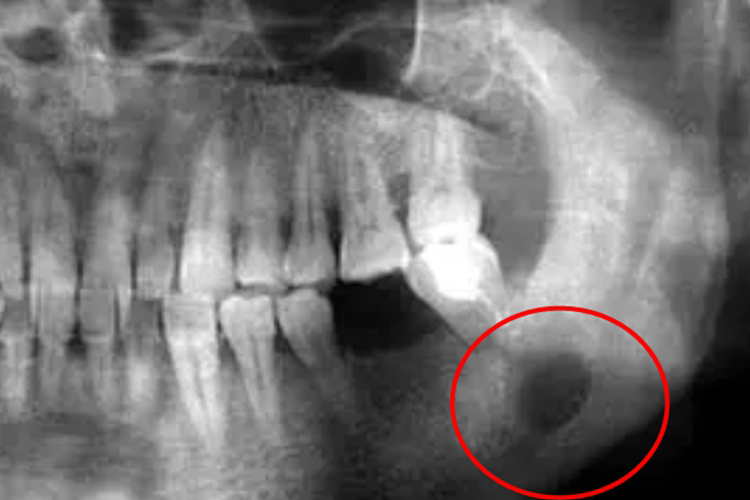

下颌骨骨化纤维瘤主要表现为颌骨呈膨大状态,肿瘤质硬,界限不清,可造成面部畸形、咬合紊乱,有时可继发感染,伴发骨髓炎。影像检查表现为类圆形肿块或不规则形肿块,多可见完整包膜。